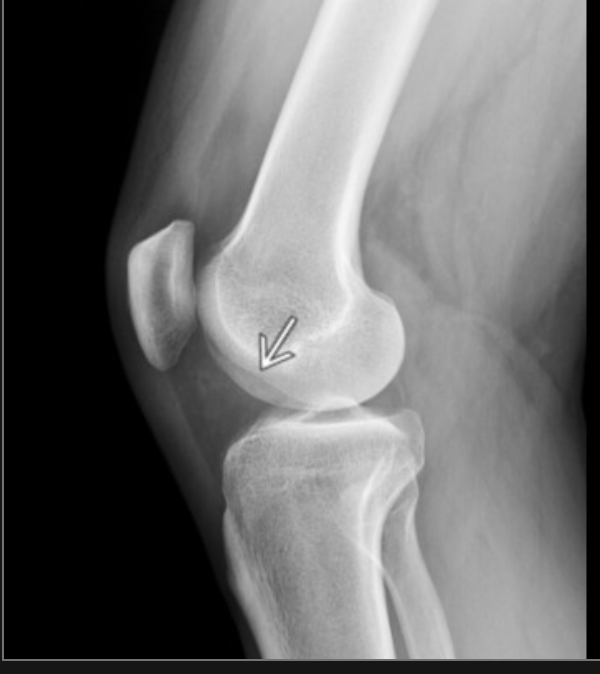

what is this structure

lateral femoral condylar recess OR condylopatellar sulcus

so its the left femoral condyle

if this is >2mm it is suggestive of ACL injury